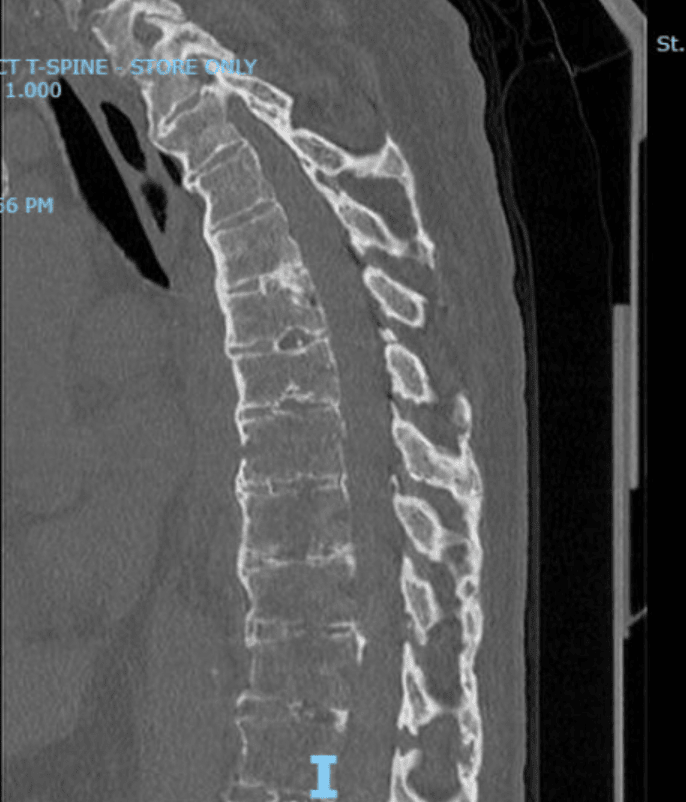

CT Scan and X-Ray After Fusion Surgery for Ankylosing Spondylitis

CT scan (Left) and X-ray (Right) of the above patient after fusion surgery.

Spinal fusion. Spinal fusion stabilizes the spine with rods, bars, or screws (hardware). The goal of spinal fusion is to reduce pain by reducing the stress on your nerves in your back. It can help the spine be more stable and correct deformities in the spine. In some cases, fusion surgery does not help pain, and hardware can sometimes cause complications, such as a fracture in a vertebra or problems in the surrounding disks and tissues over time.